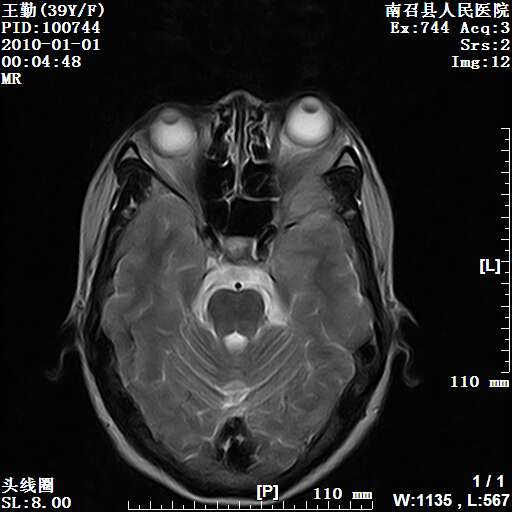

以下是引用随光逐影在2010-1-22 9:03:00的发言:[br]考虑左侧中颅窝(蝶骨翼区)脑膜瘤侵犯蝶骨翼并突入左侧眼眶。

以下是引用水过无痕在2010-1-22 14:55:00的发言:[br]一、定位:颅外占位;二、定性:恶性可能性大;三、组织来源:来源于左侧眼外直肌或其他部位;考虑为:横纹肌肉瘤>转移瘤>脑膜瘤.